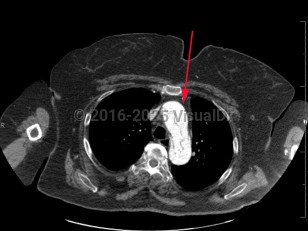

Aortic dissection is an intramural tear of the aorta. Aortic dissection is a life-threatening emergency. Tears often occur in the intimal layer of the aorta, with blood collecting in the medial layer. Back pain is the common presenting symptom, but it may also present with chest pain, dyspnea, or a new neurologic deficit. Syncope and hypotension occur less frequently. Aortic dissections most often occur in older men.

- Type A – dissection involving ascending aorta

- Type B – dissection that does not involve ascending aorta (ie, aortic arch and descending aorta)